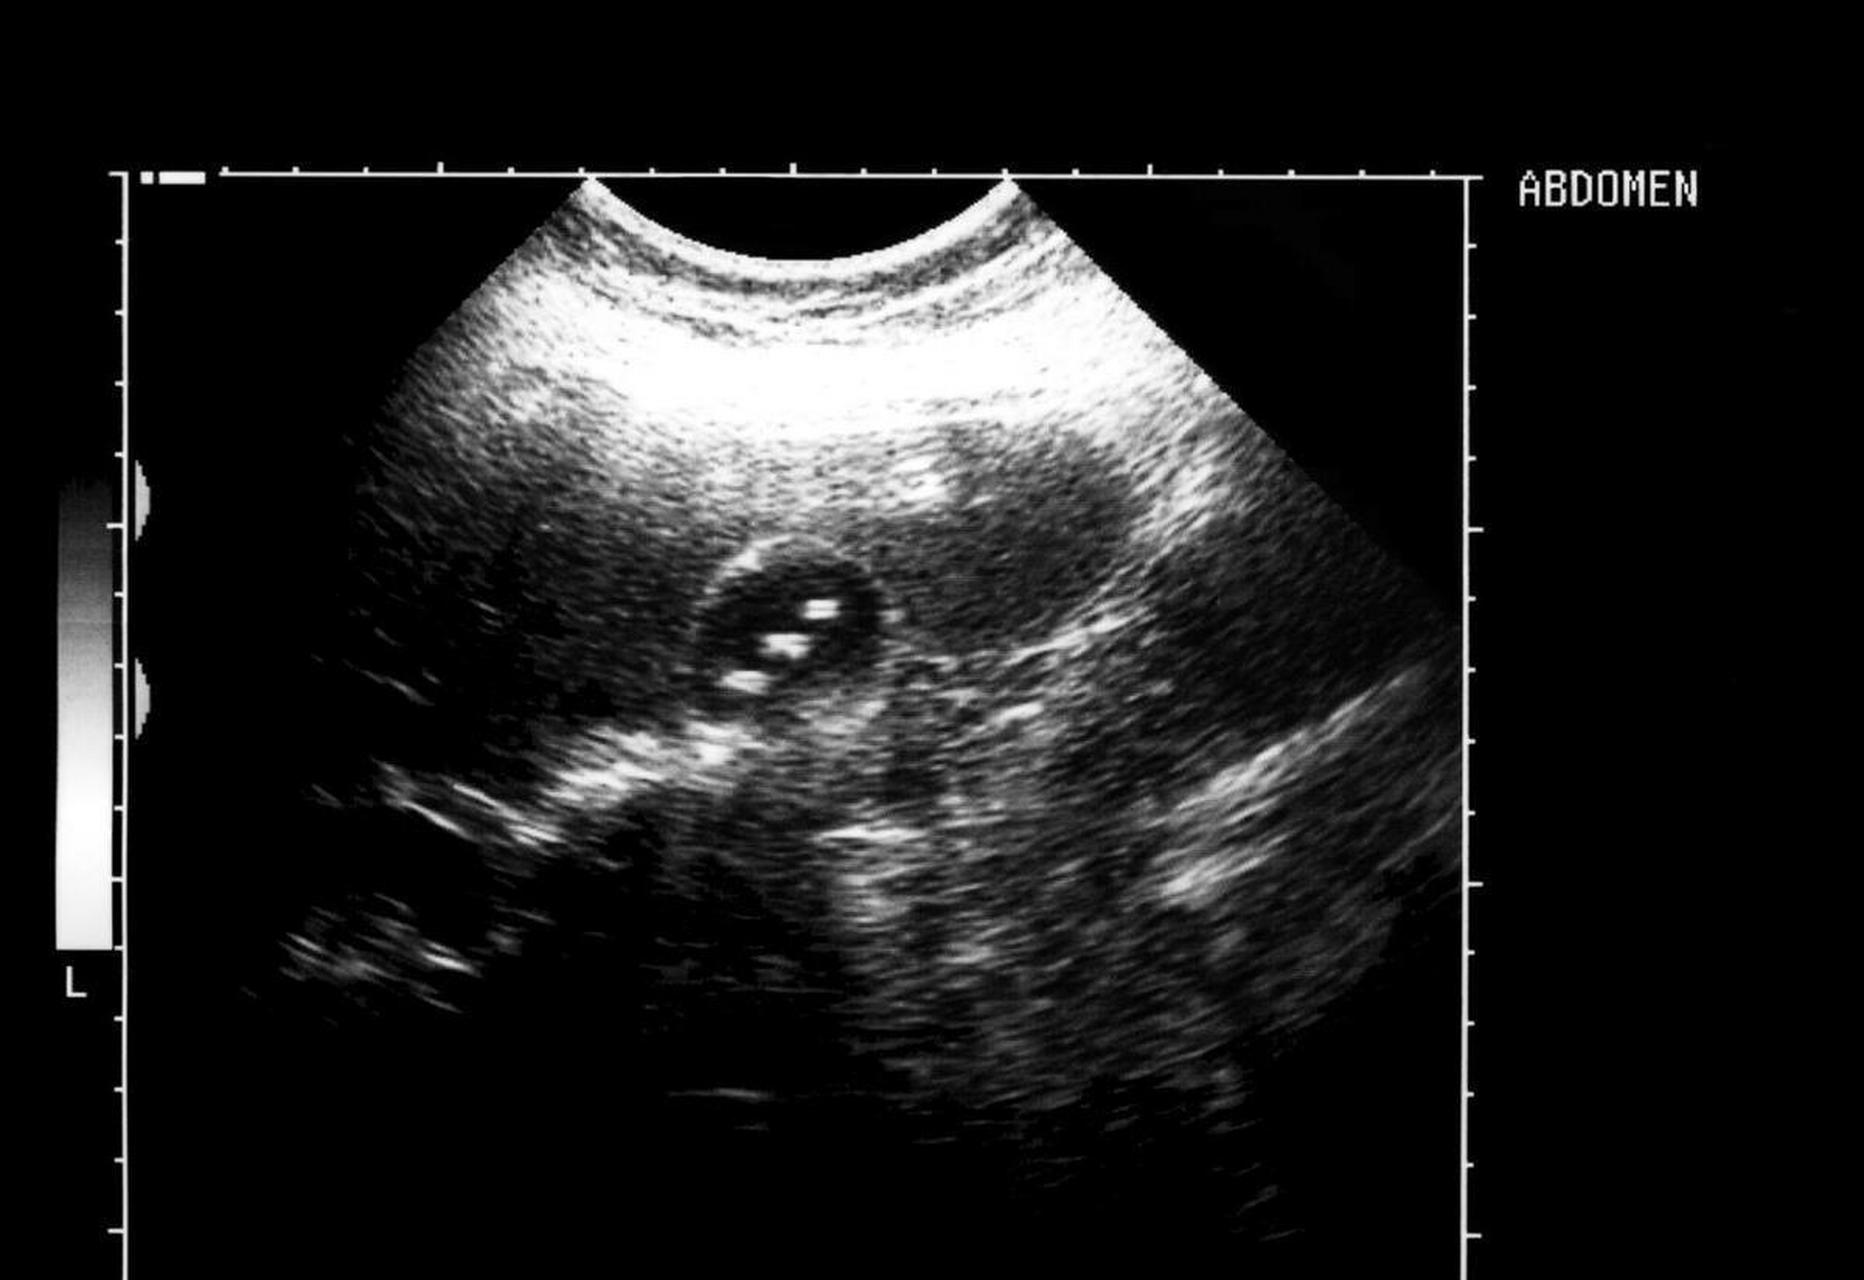

胆囊结石彩超图

胆囊结石,超声表现是这样的

胆囊结石,超声这样表现